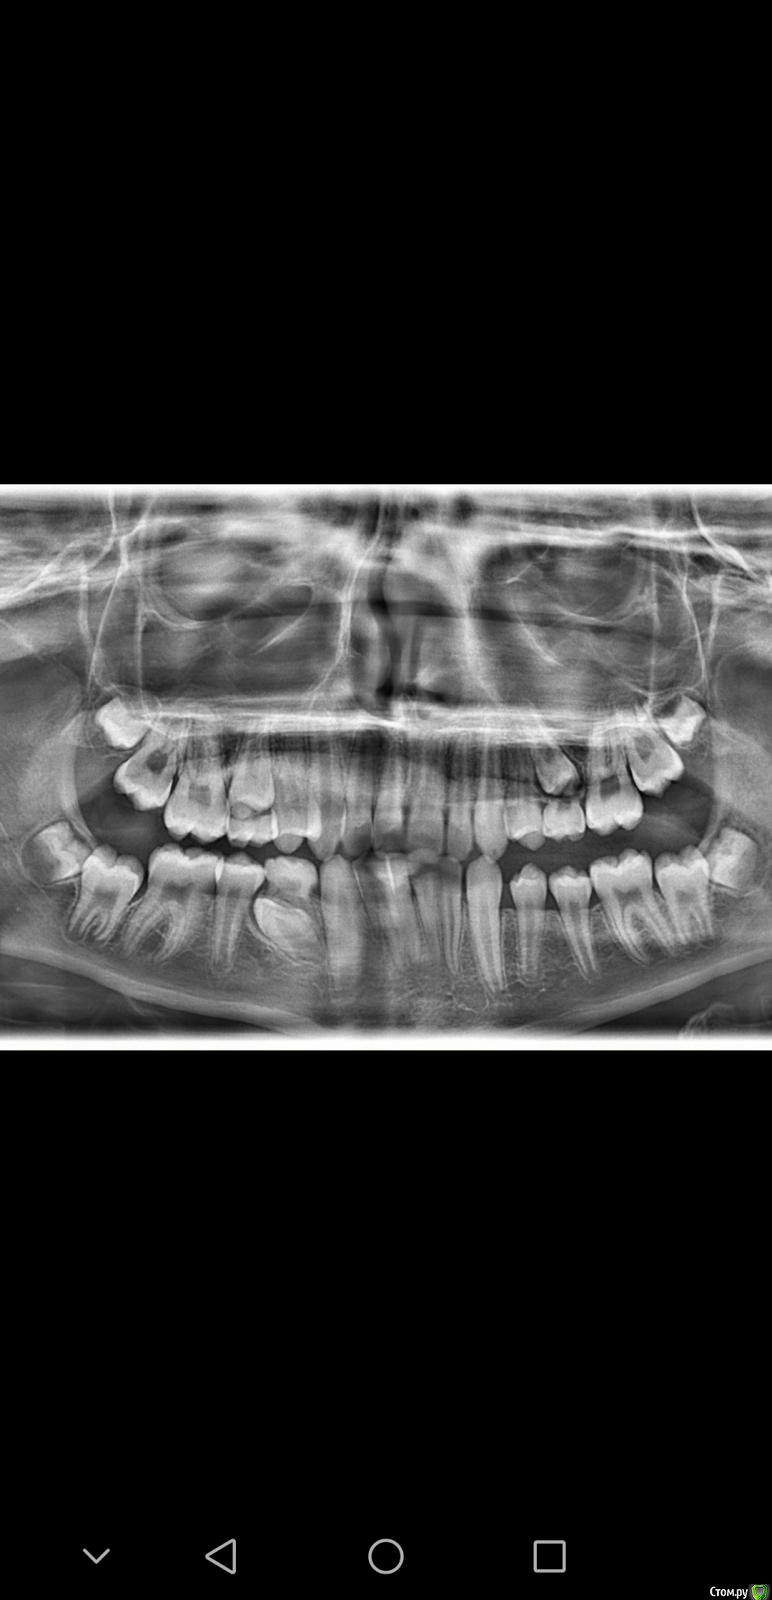

Chasiridou Опубликовано 19 февраля, 2020 Поделиться Опубликовано 19 февраля, 2020 посоветуйте терапию пожалуйста. мальчик 12 лет, верхняя челюсть выдвинута на 0.9 см вперед. снимки прилагаю. Ссылка на комментарий